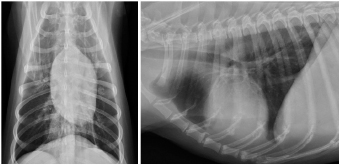

A 14-year-old spayed female Labrador retriever weighing 21.3 kg was referred to our hospital with a main complaint of chronic right-hind lameness. This patient had undergone surgery for right tibial fracture repair with implantation of bone plate and screws at a referral hospital 12 years ago. The patient showed no appetite, was not drinking, and was lethargic, with a body condition score of 1/5. The patient was unable to stand up on her own, her right hind limb was mostly weak, and she was unable to move independently using her left side. The patient’s state of consciousness was normal. On physical examination, her vital signs were normal (temperature: 38.1°C, pulse 104 beats/minutes with no heart murmur, respiratory rate with normal lung sounds: 32 beats/minutes). The mucous membrane showed a pale color because of severe anemia (packed cell volume 20.4%). In addition, the capillary refill time was delayed by <3 seconds, suggesting severe dehydration. The patient showed swelling and was warm to the touch from the right tibia to the femur, with a swollen right popliteal lymph node, which presented with a ruptured mass lesion approximately 7 × 10 cm in size. The thoracic radiograph was normal (Fig. 1). However, the right hind limb radiograph showed an osteolytic lesion accompanying the ruptured implant and loosening of the plate and screws, with surrounding soft tissue swelling (Fig. 2). Fine needle aspiration from this site suggested OSA (data not shown). Although we could not perform angiographic computed tomography because of the owner’s dissent, we performed amputation from the hip joint on the same day. Gross morphology showed severe inflammation surrounding soft tissues, the rupture of the stainless-steel bone plate, and we noted a non-medical band at the right tibia (Fig. 3). The patient was formally diagnosed with OSA after histopathological examinations (Fig. 4). After 24 hours hospitalization, we administered ampicillin potassium (20 mg/kg, BID) intravenously and prednisolone (0.5 mg/kg, SID) subcutaneously for postoperative care. Also, 24 hours continuous rate infusion of fentanyl (5 μg/kg/minutes) in lactated Ringer’s solution was used for analgesia. The patient was discharged to the owner the day after surgery for home care. The owner refused postoperative radiation therapy and chemotherapy. Unfortunately, this patient died 1 month after amputation.

Fig. 1. Thoracic radiographs.

No metastasis was observed.